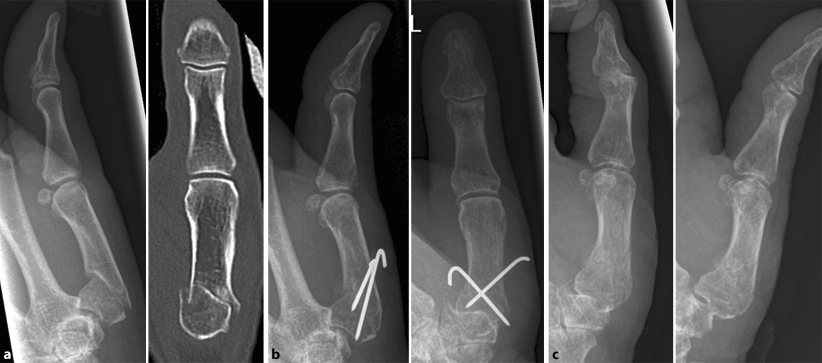

Die Röntgenbilder zeigen das Ergebnis nach 13 Jahren.

Die Röntgenbilder zeigen das Ergebnis nach 13 Jahren. from www.zweymueller.at